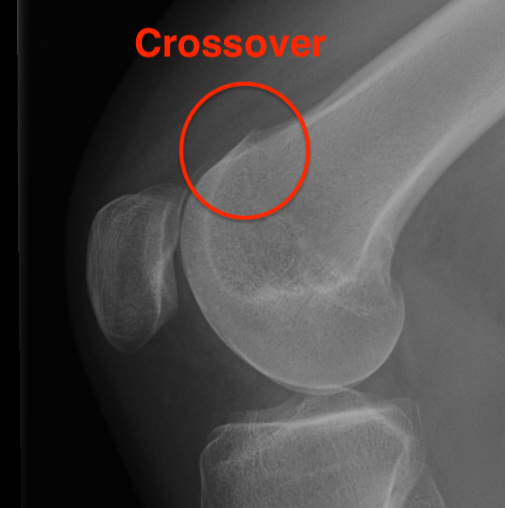

Trochlea Dysplasia / Dejour Crossover Sign

- lateral x-ray at 30o with condyles superimposed

- identify base of trochlea

- normal: clearly defined trochlea groove

- abnormal / Crossover: line of floor of trochlea crosses lateral lip of condyle

Normal trochlea / no crossover